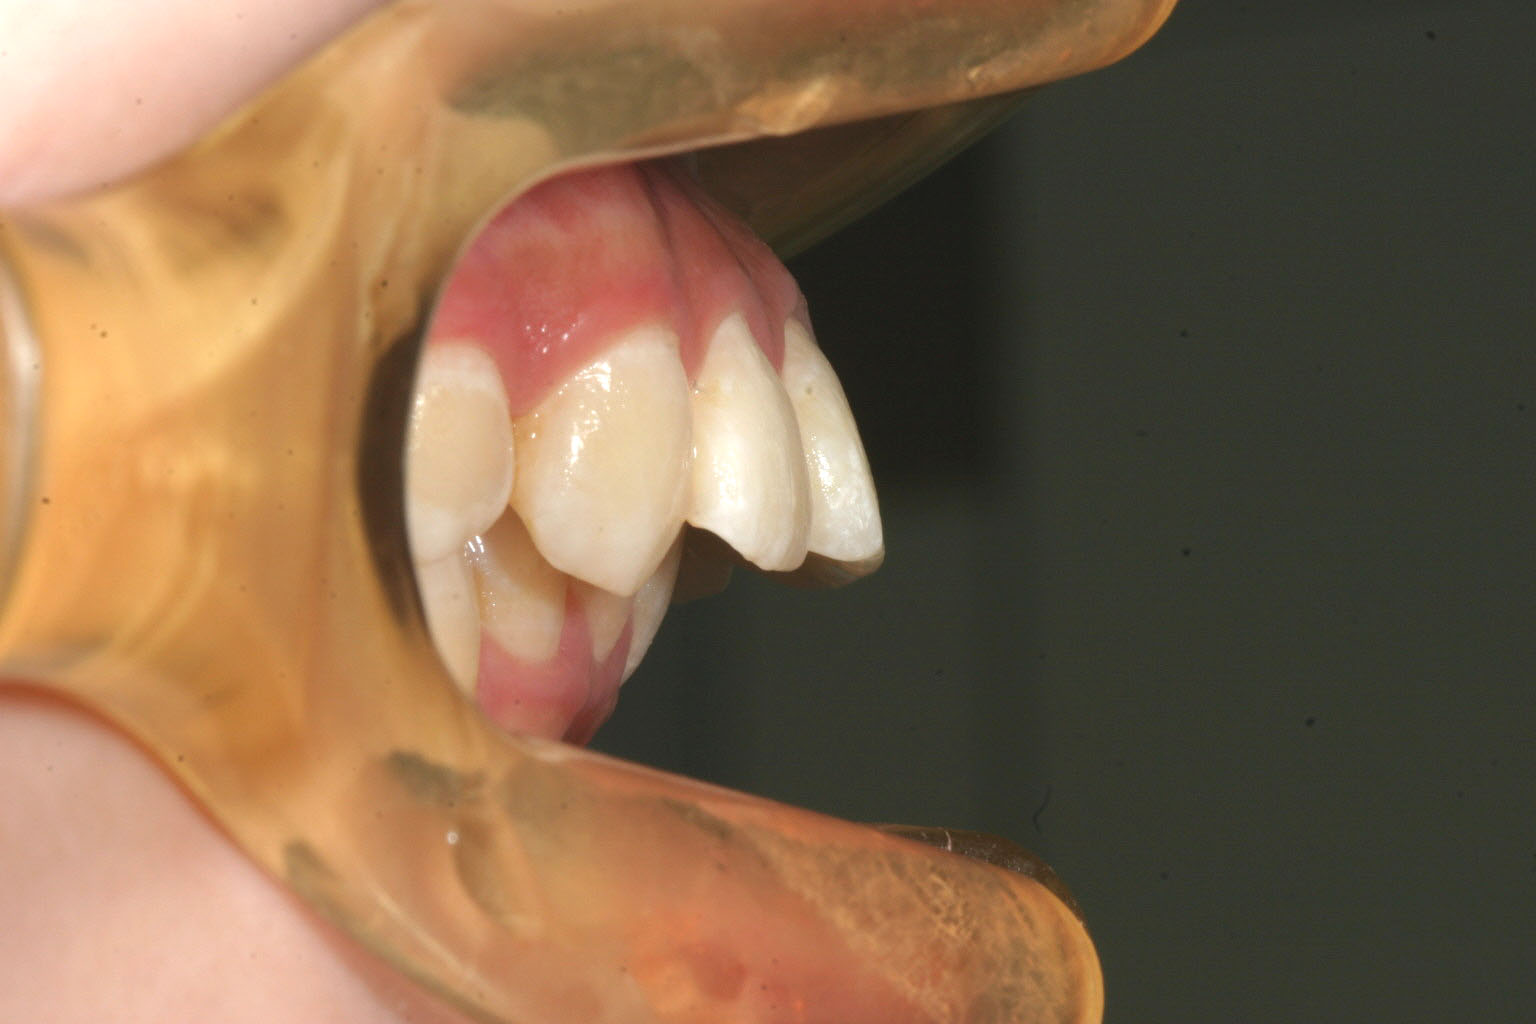

でっぱがすごくて下唇に跡形が付いて痛い。

かなりの出っ歯です。

今回の症例は過度の上顎前突の上顎小臼歯抜歯による矯正症例です。

こちらの症例は上顎が下顎に比べて全体的に前方に移動していた為、やむなく上顎の左右小臼歯抜歯を行いました。